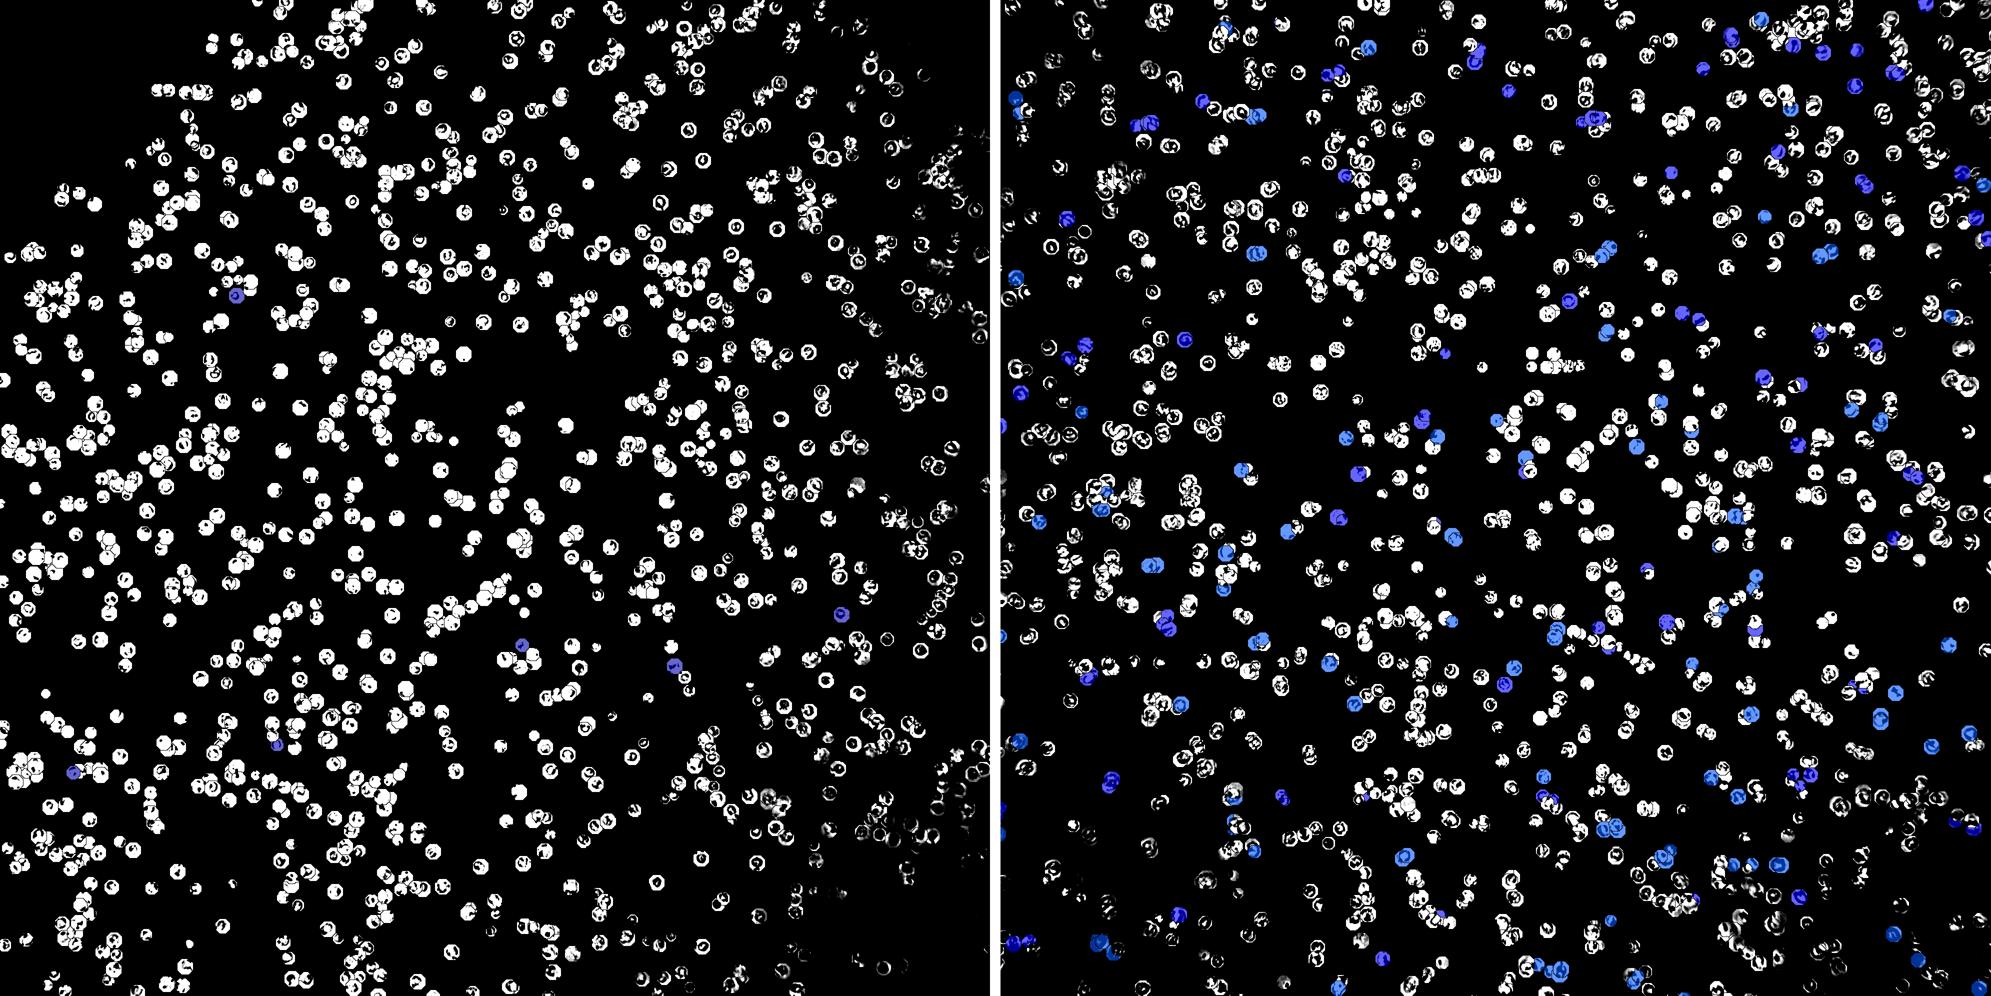

Cells labelled with CD15 TIA1

Peripheral blood lymphocytes

Inflammatory Disease

Cell populations before and after treatment